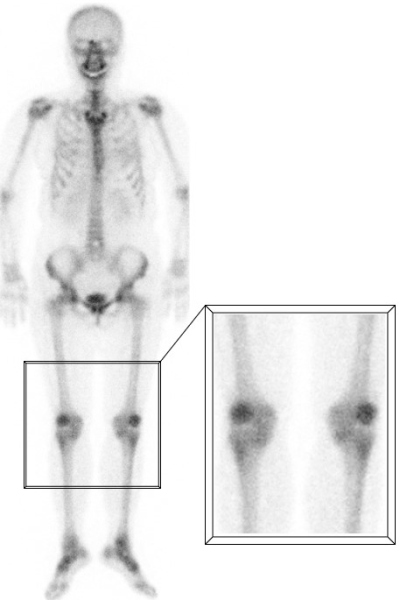

F) Captación rotuliana

Este hallazgo, conocido como "signo de rótula caliente", es extremadamente frecuente, con una incidencia que varía entre el 15 y el 31% de todos los exámenes según diferentes estudios. Puede estar asociado a cambios degenerativos, traumatismos o bursitis, entre otros factores, pero es muy común encontrarlo en individuos completamente sanos, por lo que carece de valor patológico en forma aislada(12). El aumento de captación suele ser bilateral y simétrico y probablemente represente un remodelado óseo constante secundario a la presión de las repetidas cargas a las que están sometidas las rótulas(13) (fig. 6).